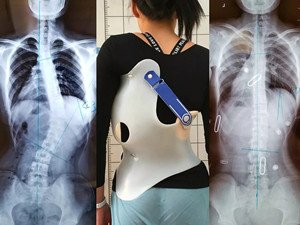

在青少年快速發(fā)育期內(nèi),身體長(zhǎng)得越快,脊柱側(cè)彎的進(jìn)展就越快。矯形支具通過(guò)長(zhǎng)時(shí)的反向矯正力將脊柱維持在一個(gè)矯正的狀態(tài);然而由于長(zhǎng)時(shí)間地佩戴支具會(huì)導(dǎo)致肌肉萎縮,當(dāng)支具摘除,脊柱側(cè)彎回彈,且患者無(wú)法形成成自我矯正力,呼吸功能亦無(wú)法得到改善。最好是在穿戴支具的同時(shí),配合體操訓(xùn)練,通過(guò)一系列矯正動(dòng)作以及呼吸訓(xùn)練,平衡肌力,兩者結(jié)合不但可以穩(wěn)定脊柱,且能增加改善機(jī)會(huì)。